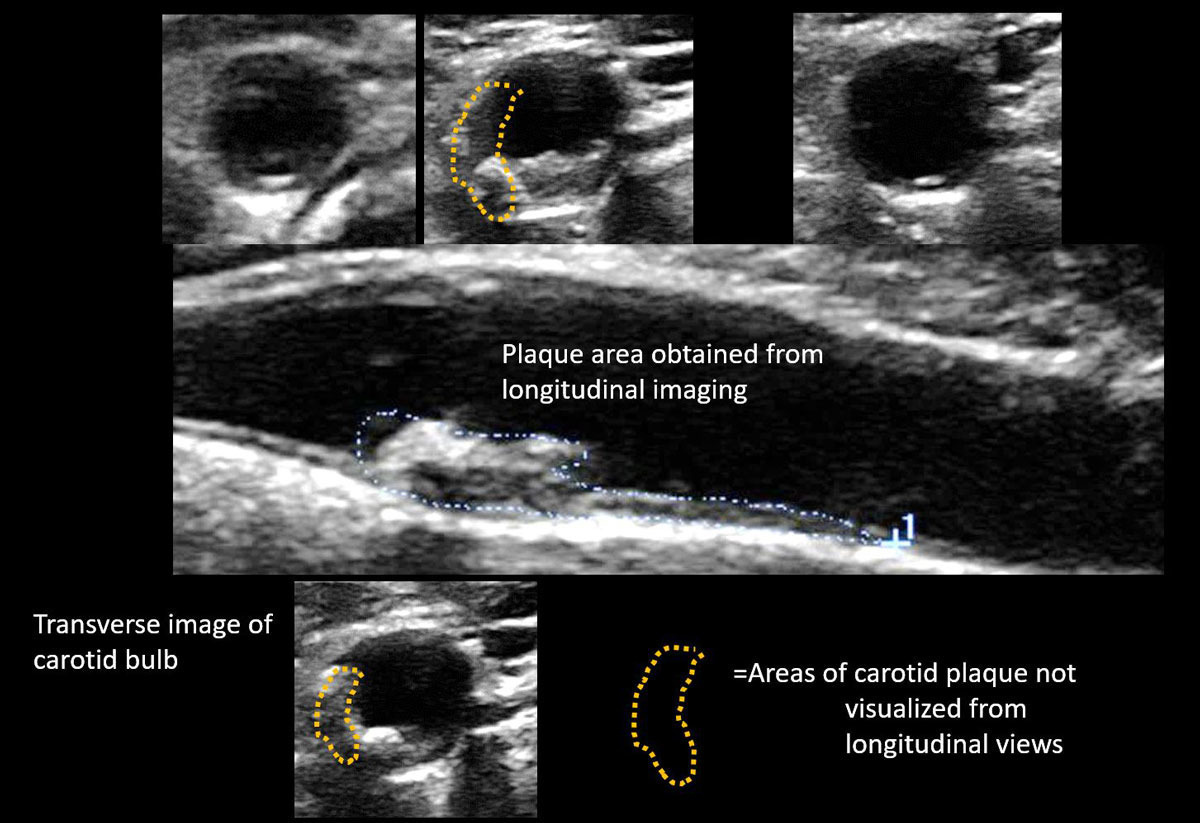

경동맥 협착증은 혈관 내벽에 콜레스테롤, 지방, 칼슘이 쌓여 혈관이 좁아지는 질환입니다. 경동맥 내경이 50% 이상 좁아지면 뇌혈류가 감소하여 뇌졸중 위험이 급격히 증가합니다. 초음파를 통해 협착 부위의 정도, 혈류 속도, 플라크의 성질(단단한지, 불안정한지)을 정밀하게 평가할 수 있습니다.

경동맥 초음파 검사는 동맥경화의 초기 단계를 확인할 수 있습니다. 혈관벽이 두꺼워지는 ‘내중막 두께(IMT, Intima-Media Thickness)’를 측정하여, 향후 심혈관계 질환 위험도를 예측합니다. IMT가 0.9mm 이상이면 동맥경화 진행이 의심되며, 1.5mm 이상이면 플라크 형성이 진행된 것으로 봅니다.

경동맥 초음파 검사는 준비 과정이 간단합니다. 공복 상태일 필요가 없으며, 목 주변의 금속 액세서리나 목도리만 제거하면 됩니다. 검사 시간은 약 10~20분 정도이며, 환자는 눕거나 고개를 약간 돌린 상태로 검사를 진행합니다. 탐촉자를 목 부위에 대고 초음파를 투사하면 화면에 경동맥의 단면이 실시간으로 나타나며, 의사는 혈류 속도와 벽의 상태를 분석합니다. 혈관이 막혀 있거나 좁아진 부분에서는 혈류 속도가 비정상적으로 증가하므로, 이를 통해 협착의 정도를 정량화할 수 있습니다.